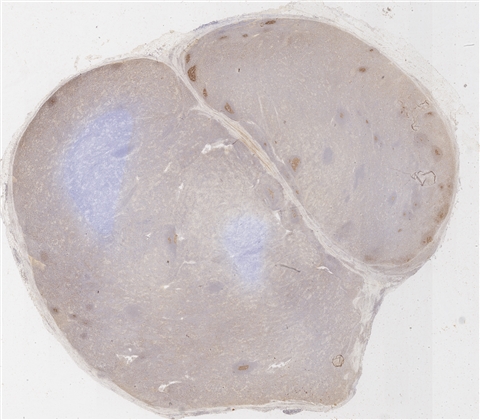

案例4 (6863)

性别:       年龄:48

患者详情: 患者4月余前体检行胸部CT检查示“右肺上叶混杂磨玻璃结节;纵隔多发肿大淋巴结可能”。3月前来我院门诊就诊,行胸部CT示“中纵隔右侧肿块,请结合穿刺;右锁骨区、纵隔及右肺门多发肿大淋巴结”。行纵隔肿块EBUS,显微镜下“见纤维素样渗出物及少量淋巴细胞、纤维样细胞及支气管上皮细胞,未见恶性依据”。行PET-CT检查示“右纵隔右侧肿块,FDG代谢增高;纵隔、双侧锁骨上小淋巴结,FDG代谢增高”。遂行纵隔肿块切除术。

大体所见: 送检“中纵隔肿瘤”一枚,大小5.5*4.5*4.0cm,包膜完整,切面灰黄质韧,中央见灰白星状瘢痕。

医院: 复旦大学附属肿瘤医院